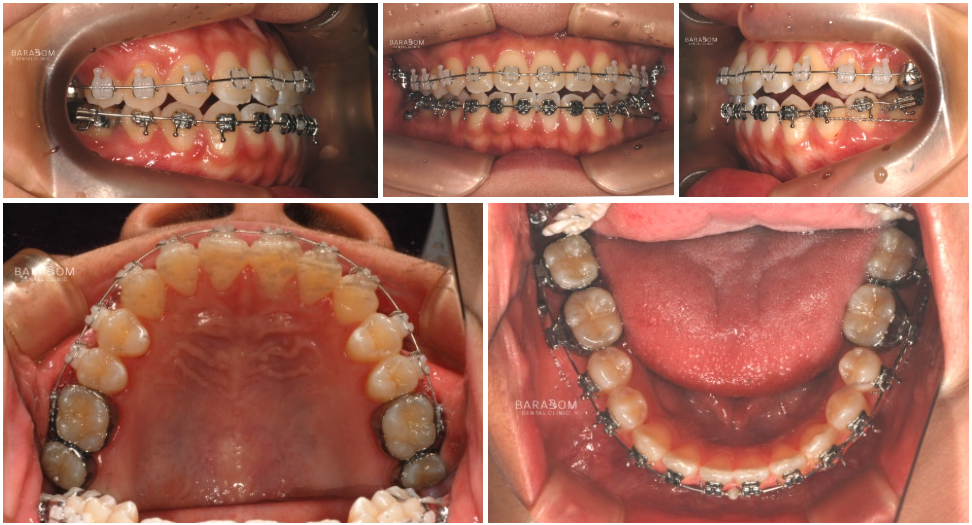

장치(브라켓)를 달고

변위된 치아를 제 자리로 이동시킴과 동시에

아랫치열을 후방으로 밀기 시작합니다.

그래야 안정적인 교합을

유도할 수 있기 때문이죠.

아랫 치열을 당기는 힘을

조절하기 위해서 스프링을 사용합니다.

✔동시에 어금니는 정출 즉,

위로 올라오도록 유도하고

아래턱은 시계방향으로 회전하여

전치부의 정상적인 맞물림을 위해

윗쪽 앞니의 정출을 유도합니다.

더불어 미니 임플란트를 활용하여

아래 치열의 후방 이동을

더욱 확실하게 유도합니다.

이와 더불어 3급 부정교합임에도 2급 고무줄을 활용하여 긍정적인 변화를 유도합니다.

✅대개 2급 환자에게 시행되지만

이 경우 맞물림을 시계방향으로

회전하는 과정이 필요하여 적용하는 것입니다.

입술(순측)으로 경사를 이루던 앞니를

설측(혀)가 있는 쪽으로 기울어지게 유도하고,

이와 더불어 씹는면 쪽으로 정출되도록

움직임을 만들어냅니다.

이 과정은 정말 세밀한 조절이 필요합니다.